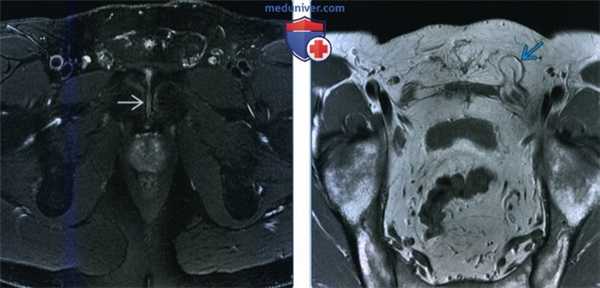

(Слева) МРТ Т2ВИ, режим подавления сигнала от жира, аксиальный срез: у профессионального игрока в гольф 42 лет с болью в паху определяется отек и неровность вдоль лобкового симфиза, указывающие на остеит лобковой кости легкой степени.

(Справа) МРТ Т1ВИ, косой аксиальный срез: у этого же пациента определяется жировая клетчатка непрямой паховой грыжи, выходящей через паховый канал. Такие признаки являются случайными, поскольку симптомы у данного пациента связаны в большей степени с остеитом лобковой кости, который определялся на предыдущей томограмме.